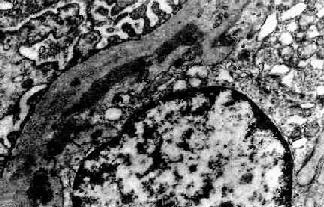

图12-13 膜性增生性肾小球肾炎

肾小球系膜细胞增多,增生的系膜组织侵犯毛细血管,毛细血管壁增厚,腔狭小,肾小球丛呈分叶状

电镜观察可见肾小球系膜增生,毛细血管基底膜不规则增厚。增生的系膜组织沿毛细血管基底膜和内皮细胞之间向毛细血管周围部分伸展,甚至环绕全部毛细血管壁,使毛细血管壁增厚。肾小球内有大量电子致密物沉积。根据沉积物的部位,可将膜性增生性肾小球肾炎分为3型:

图12-15 膜性增生性肾小球肾炎 Ⅰ型

肾小球毛细血管基底膜内侧,内皮细胞下电子致密沉积物,部分上皮细胞足突消失